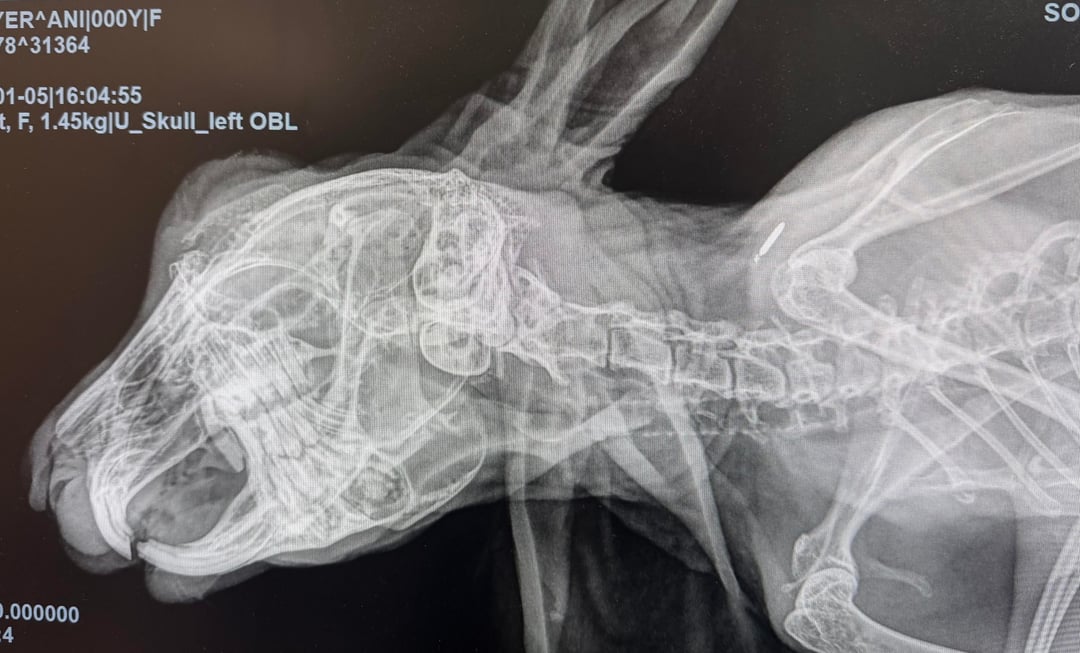

Took our baby (5.5 years old) to the vet for a routine check, and the vet was very concerned about the abscess found in her lower left jaw. He wants to extract all her lower left teeth and drain the abscess from the inside.